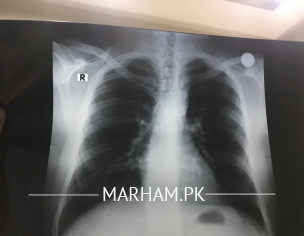

Talk to Chest Respiratory Specialist on Please Check Chest X-ray

Doctor please check my chest x-ray

X-ray is normal

what are the symptoms ??

Okay , nothing to worry

Your X-ray appears to be quite normal, showing no active lung disease.